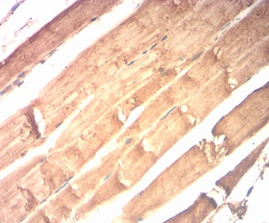

IHC    1/200 - 1/1000